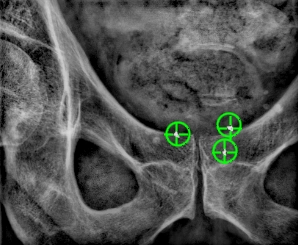

Prostate

Fiducial markers are often used to guide external beam radiotherapy for prostate to provide target coverage while protecting nearby sensitive organs. The fiducial markers can be used for the treatment planning, daily patient setup and for intrafraction motion management during treatment. Using fiducial markers for prostate radiotherapy have proven to increase accuracy, reduce side effects and improve treatment outcome.

Gold Anchor’s industry leading thin needles and unique anchoring marker design makes it possible to proceed with CT/MR for dose planning on the same day as implantation. The Gold Anchor markers are also visible on MRI due to unique and patented material. Gold Anchor can also be tracked in real-time during treatment with kV-imaging.